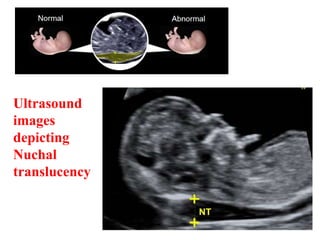

 Nuchal Translucency- Increased fetal nuchal

skin thickness (in first trimester) > 3 mm by

TVS is a strong marker for chromosomal

anomalies ( trisomy 21, 18, 13, triploidy and

Turners syndrome)

Ultrasound

images

depicting

Nuchal

translucency